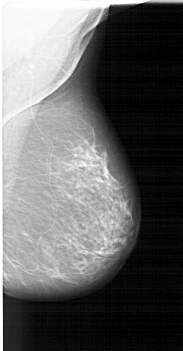

A_1410_1.LEFT_CC

LEFT_CC LINES 5551 PIXELS_PER_LINE 3256 BITS_PER_PIXEL 12 RESOLUTION 43.5 OVERLAY